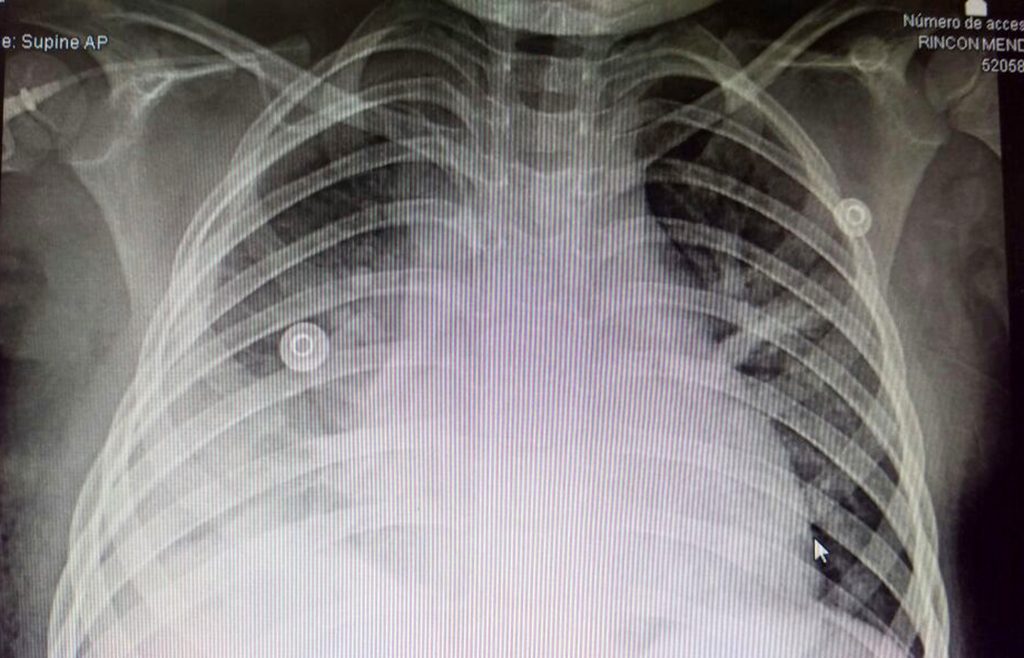

Ahí, tras estudios de Rayos X, se determinó que la menor tenía acumulación de líquido en el tórax a consecuencia de una bacteria que le produjo neumonía, por lo que fue trasladada de emergencia al Hospital General de Zona No. 1 en Villa de Álvarez, para su mejor atención.

A su llegada, los especialistas realizaron diversos estudios y colocaron una sonda para eliminar el líquido del pulmón, procedimiento que llevaron a cabo durante cinco días para drenar todo el líquido posible; ante la persistencia de la fiebre y la imposibilidad de limpiar toda el área afectada, se decidió realizar una intervención quirúrgica.